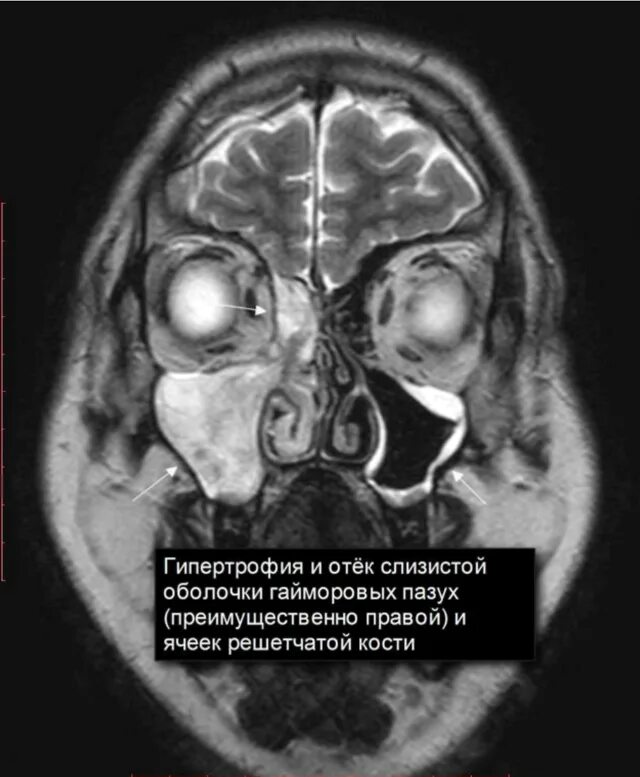

Как лечить утолщение слизистой верхнечелюстной пазухи